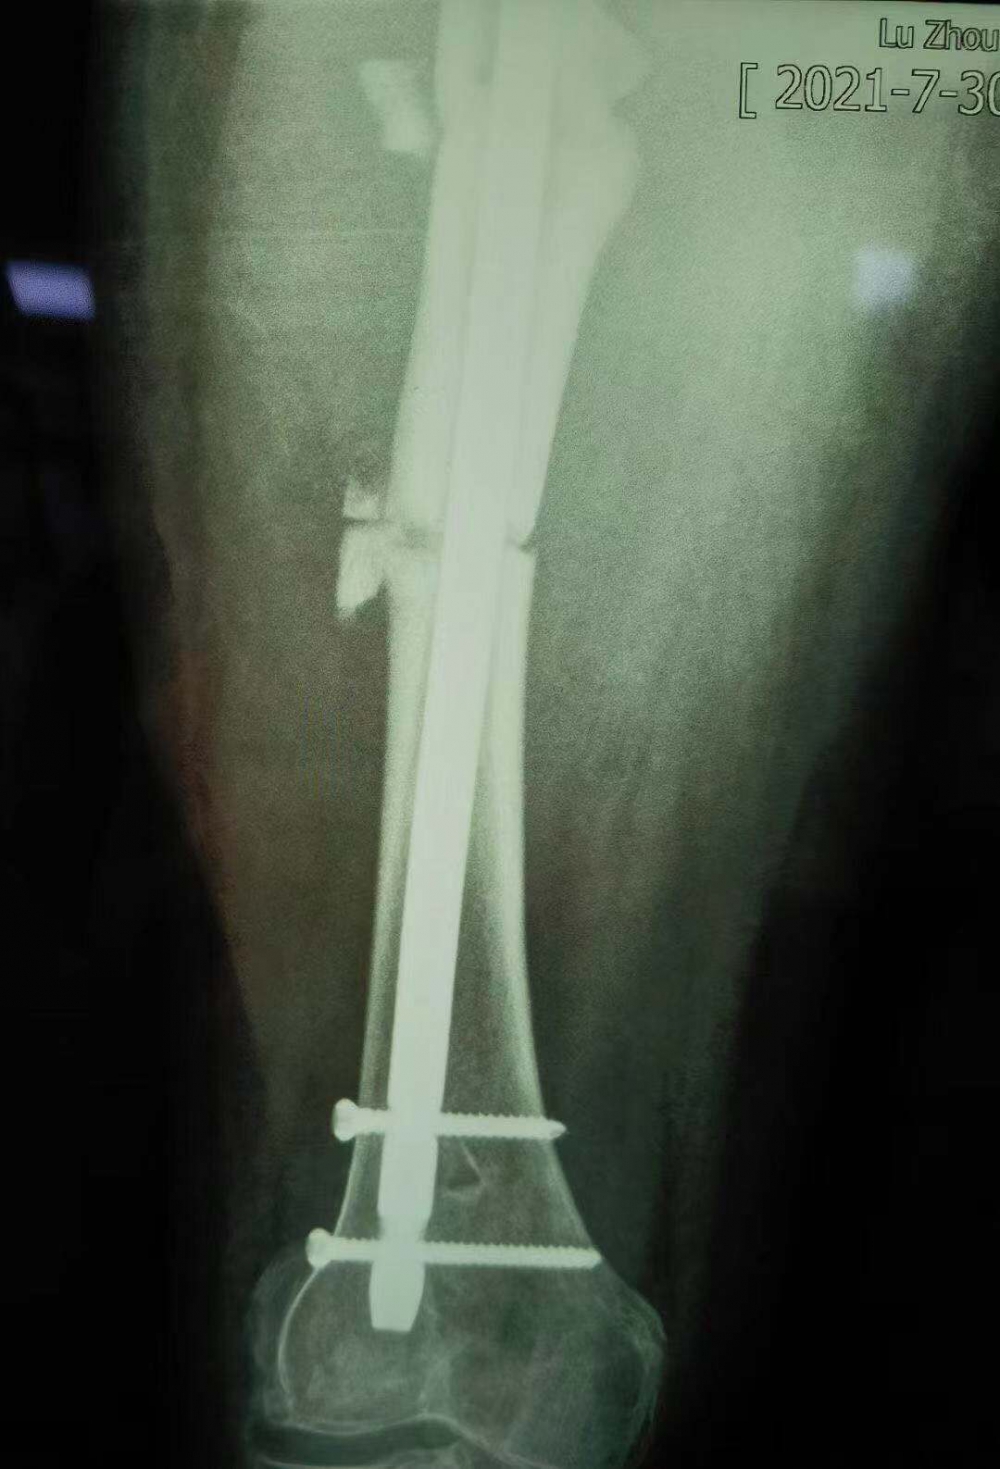

术后拍摄的X光片

但因张女士属于股骨上段骨折畸形以后手术归正,整个股骨头的负重区已经发生了一些改变,髋关节关节炎也可能存在,因此张女士还需进行后续的康复性治疗和护理。